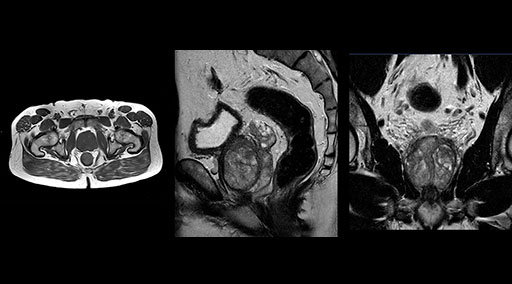

Patrick Duffy BS, RT (R) MR is Lead Technologist at DMG. “We are getting phenomenal image quality on all types of exams,” he says. “Our MSK is stellar, and so is our abdominal work. Ingenia excels at feet, hands and fingers. We do enterographies with great results. With the combination of the 3.0T magnet and the digital coils, we are able to scan prostates without an endorectal coil while still obtaining high quality results. This is a comforting experience for our male patients. We scan many obese patients, and the Ingenia does a tremendous job because of MultiTransmit, which reduces dielectric shading for more confident diagnosis. Our technologists really enjoy scanning on the Ingenia. We also have ordering physicians who specifically want their patients scanned on the Ingenia because of the results of our imaging.

“Without using an endorectal coil we do our prostate MR at 0.5 mm resolution, following the European society of urology protocol [1]. For certain joints we use a virtual arthroscopy protocol with 1 mm pixel size and 2 mm slice thickness. Ingenia really excels in our neurography, brachial plexus and prostate scans. Our neurologists insist on using our 3.0T for those,” Dr. Kaakaji adds.

“Our DMG Lisle location includes a cancer center, so soft tissue neck scans, brachial plexus scans, and prostate scans are common. For these exams, mDIXON TSE provides excellent images with and without fat suppression all while helping us reduce repeats and work more efficiently,” Mr. Duffy says.